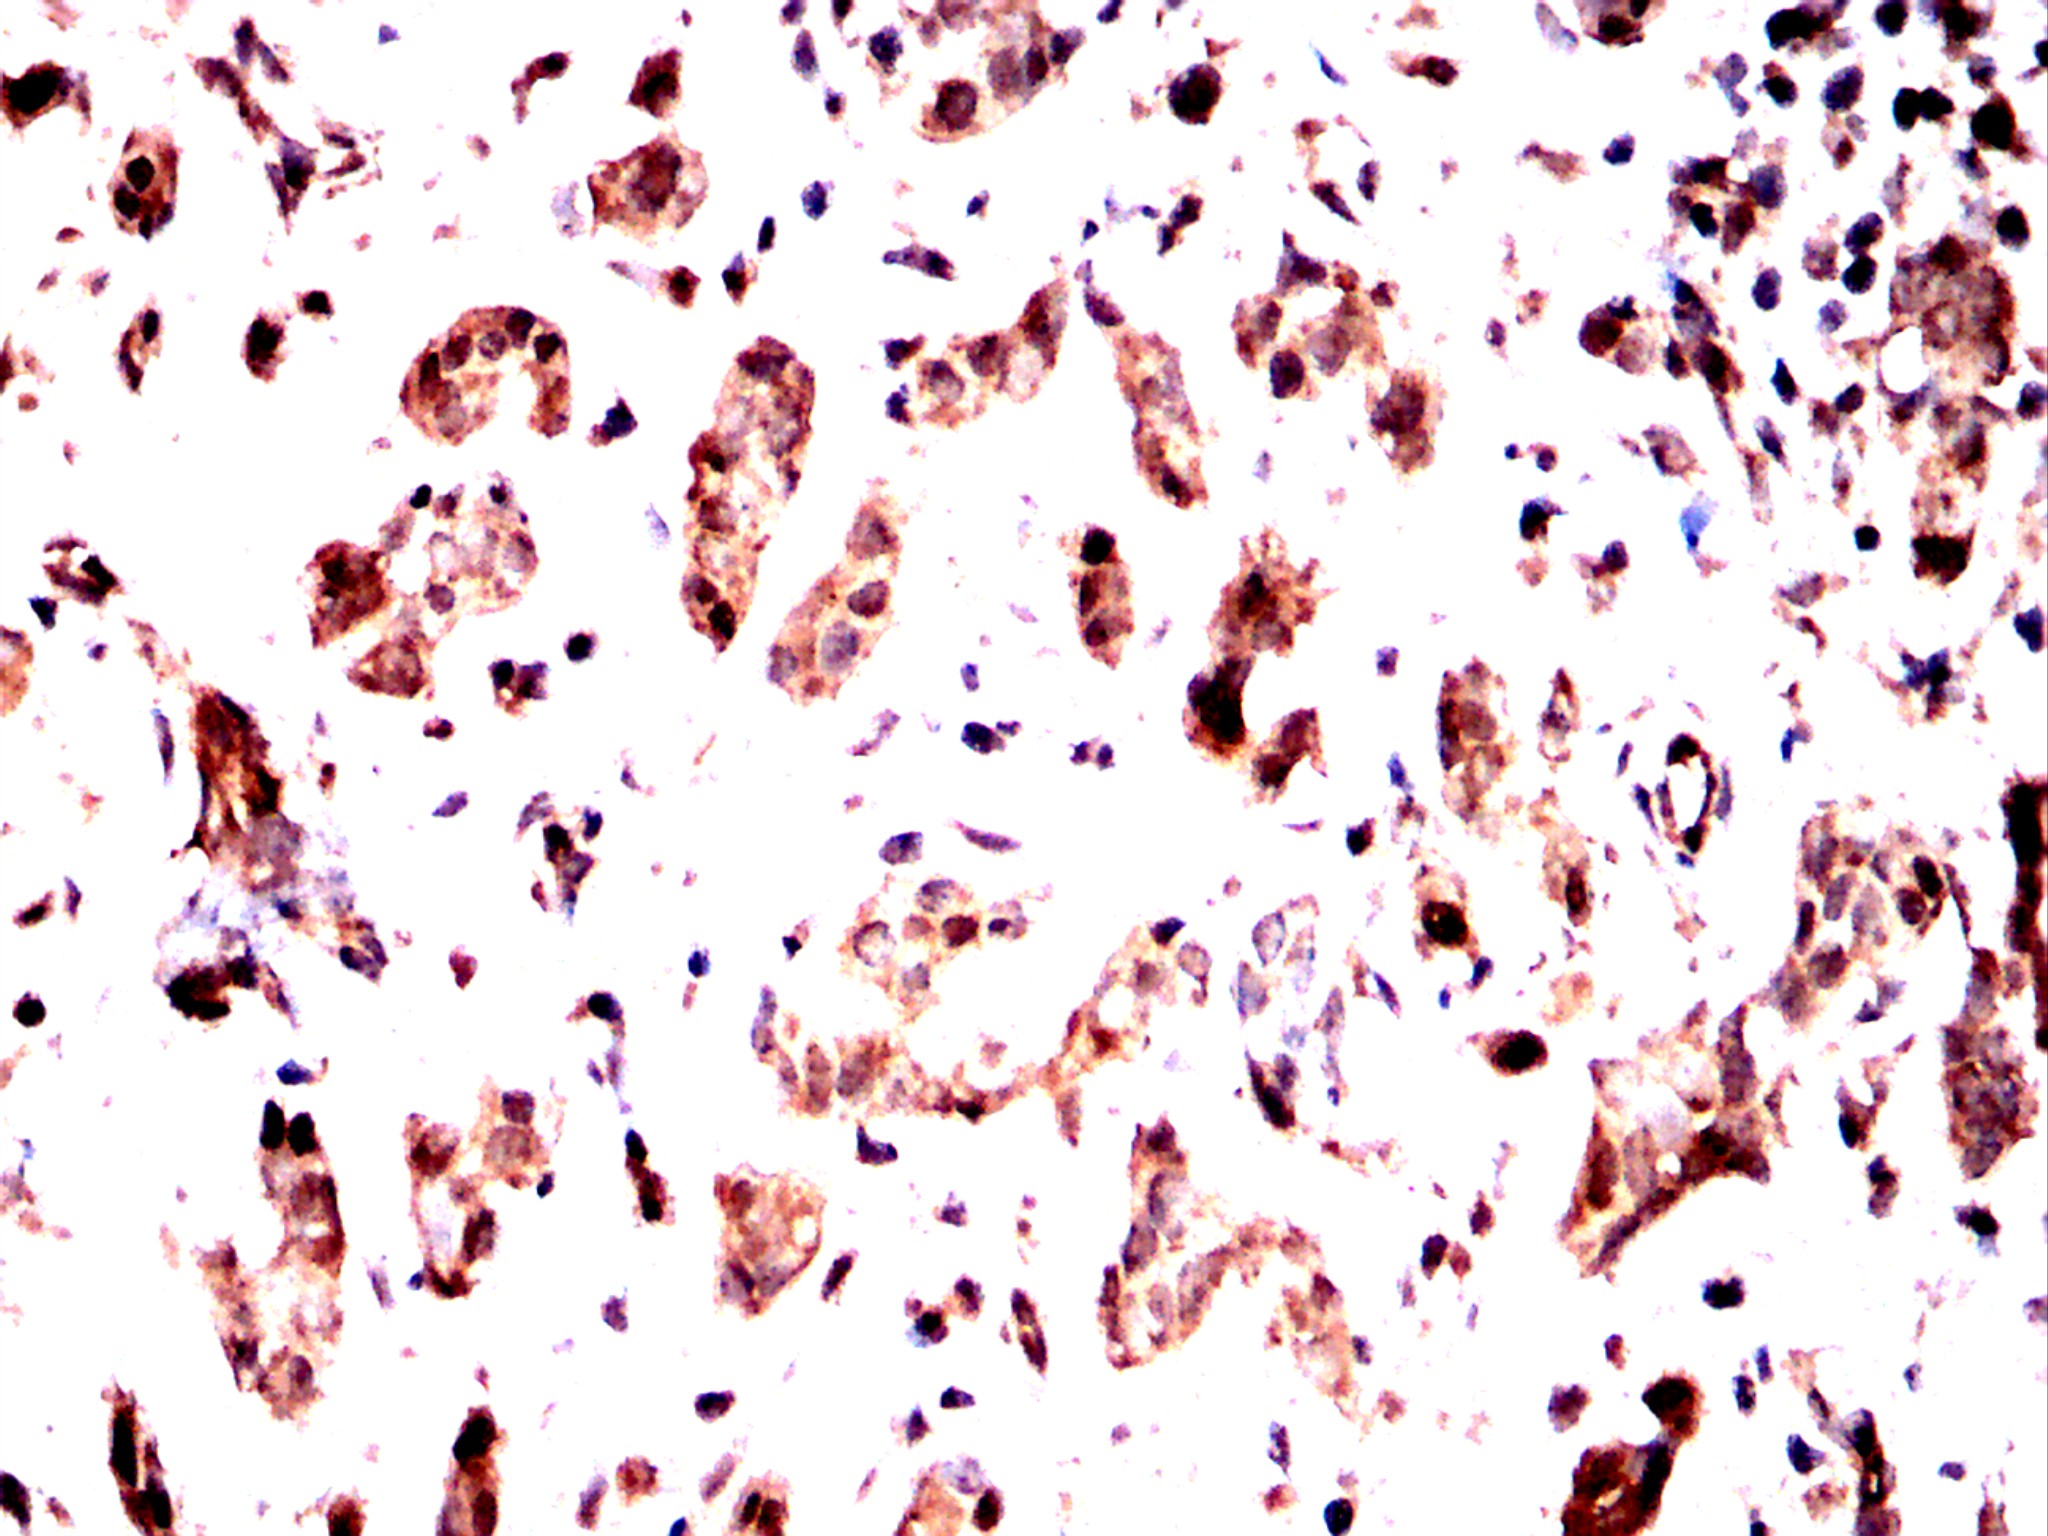

Immunohistochemical analysis of paraffin-embedded cervical cancer tissues using CBX1 antibody with DAB staining. Pre-treat the sections with heat-mediated antigen retrieval using sodium citrate buffer (pH 6.0) (OM750020) for 2 minutes. Wash the sections with ddH₂O and PBS (OM750003). Block the tissue with 10% non-immune goat serum(OM760028) at room temperature for 30 minutes. Incubate the tissue with the primary antibody diluted at a ratio of 1:1500 at 4°C overnight. At room temperature, dilute the secondary antibody, Goat Anti-Rabbit IgG(H&L)-HRP (OM644332), at a ratio of 1:200 and incubate for one hour. Use DAB(OM760029)as the chromogenic agent. Counterstain the tissue with hematoxylin, and mount the tissue sections with neutral gum.IHC

Immunohistochemical analysis of paraffin-embedded cervical cancer tissues using CBX1 antibody with DAB staining. Pre-treat the sections with heat-mediated antigen retrieval using sodium citrate buffer (pH 6.0) (OM750020) for 2 minutes. Wash the sections with ddH₂O and PBS (OM750003). Block the tissue with 10% non-immune goat serum(OM760028) at room temperature for 30 minutes. Incubate the tissue with the primary antibody diluted at a ratio of 1:1500 at 4°C overnight. At room temperature, dilute the secondary antibody, Goat Anti-Rabbit IgG(H&L)-HRP (OM644332), at a ratio of 1:200 and incubate for one hour. Use DAB(OM760029)as the chromogenic agent. Counterstain the tissue with hematoxylin, and mount the tissue sections with neutral gum.